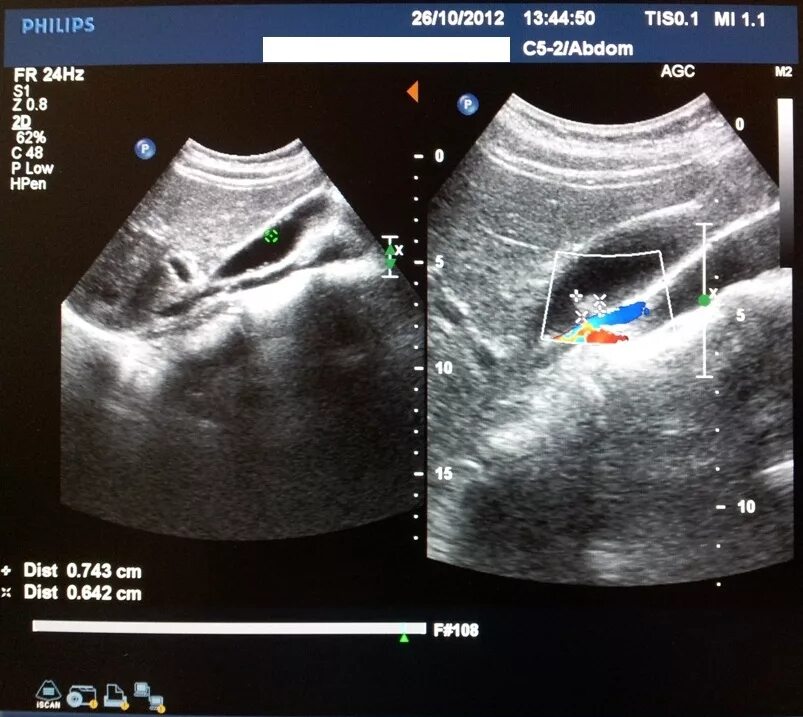

Как избавиться от полипов в желчном пузыре